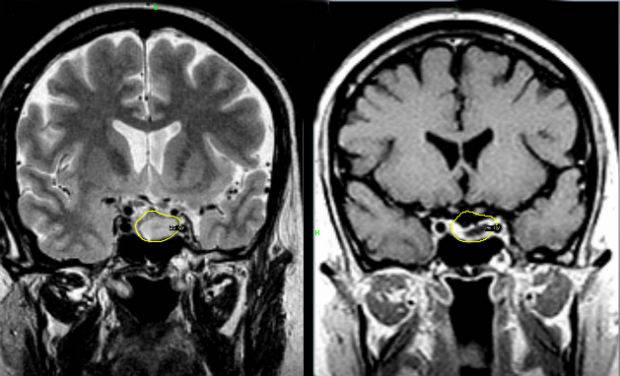

МРТ головного мозга с контрастом обязательно при диагностике онкологических процессов.

Фото: